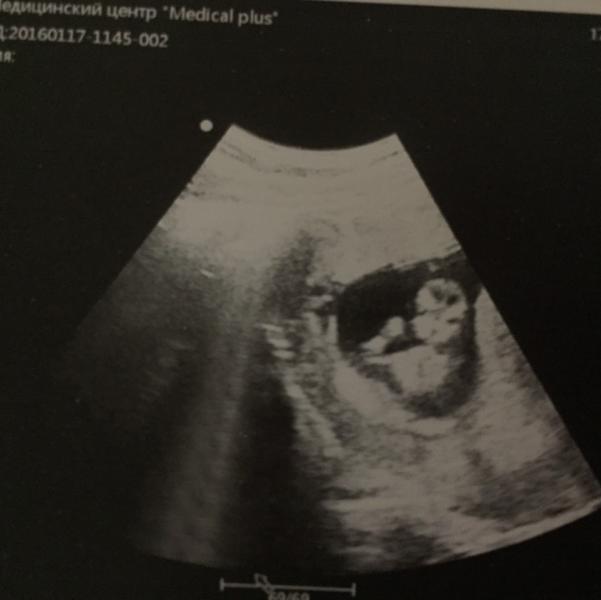

Наш первый скрининг!! 😊👼🏼❤️

Ходили сегодня вместе с мужем, благо воскресение)) по ктр 12 недель, эмоции переполняют до сих пор! Малыш сразу же нас поприветствовал - ручкой помахал (и вот сделали кадр), это было так забавно- наблюдать за его всеми шевелениями! Ни на секунду не успокаивался, дергал и ручками, и ножками, плавал вовсю) даже врач сказала, что активный малыш)) 177 ударов сердцебиение, по задней стенке прикреплён, но пока ещё есть желточный мешочек 6мм.. Поэтому токсикоз не отпускает, в ...